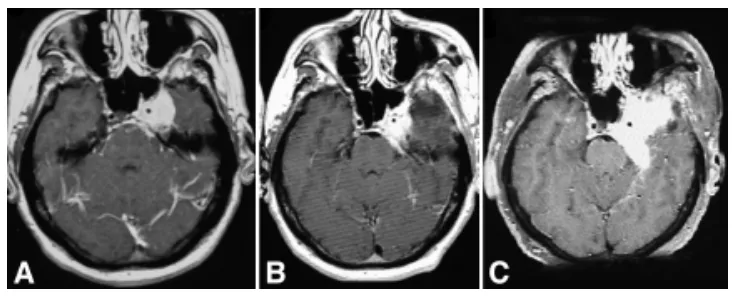

48岁男性,完全性眼肌麻痹(第Ⅲ、Ⅳ、Ⅵ对颅神经受累)伴三叉神经第一支分布区感觉减退。磁共振成像显示左侧中颅窝巨大强化占位(4.5×4.5×4.0厘米),累及海绵窦,压迫海绵窦段颈内动脉及蝶鞍,向前延伸至视神经管,向后进入左侧环池(图2A)。血管造影显示肿瘤压迫致左侧颈内动脉狭窄。

图2.48岁男性患者,表现为眼肌麻痹伴面部感觉减退,磁共振影像显示肿瘤进展。A:左侧中颅窝占位,主要累及海绵窦。B:行次全切除术。3年后MRI显示残余肿瘤进一步生长,遂行放射外科治疗。C:放射外科治疗4年后肿瘤显著生长,行再次切除术。

经眶颧入路切除左侧海绵窦脑膜瘤过程中,因球囊闭塞单光子发射计算机断层扫描显示皮层灌注缺损,未对颈内动脉壁的侵袭性肿瘤进行激进切除。术后即刻MRI显示左侧海绵窦残留肿瘤大小为1.8×1.5×1.0厘米,9个月后增大至2.2×2.3×3厘米(图2B)。3年后随访MRI显示残留肿瘤生长,遂行放射外科治疗。

放射外科治疗4年后,常规随访显示肿瘤显著增大至5.5×5.0×5.0厘米(图2C)。MR血管造影显示海绵窦内左侧颈内动脉因肿瘤包裹而狭窄。患者经左侧眶颧开颅再次手术,显微镜下切除复发性脑膜瘤的颞下及颅内部分。患者术后无新增神经功能缺损,但左侧完全性眼肌麻痹未改善。